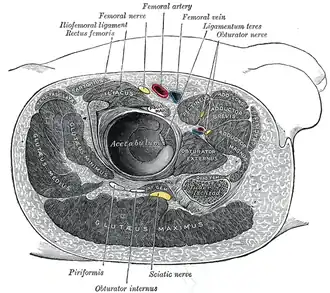

Structures surrounding right hip-joint

Structures surrounding right hip-joint -